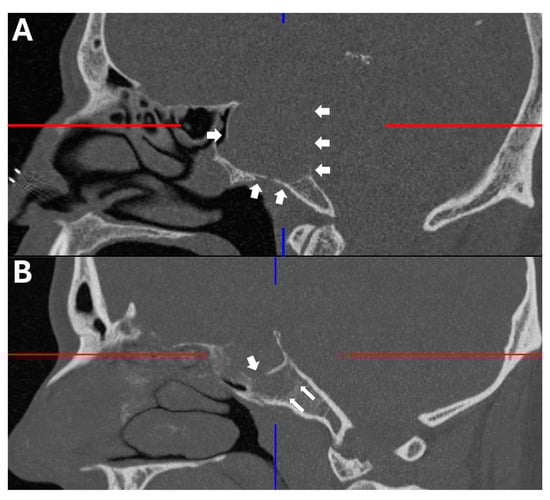

Preoperative and postoperative magnetic resonance and computerized tomography imaging were reviewed to assess tumor extension, specifically the type of clivus infiltration (focal or diffuse growth into the clivus, state of the cortical lamella), extent of resection, residual tumor and visibility of the pituitary gland. The type of sellar destruction was classified as diffuse only if almost the entirety of the sella floor was destroyed, while multifocal perforation of the sellar floor with consecutive spread into the cancellous clivus was classified as focal. In order to assess the extent of clival infiltration, three regions of tumor growth along the clivus were defined (Figure 2 and Figure 3): along the dorsum sellae from the posterior clinoid processes to the floor of the sella (region I), from the sellar floor to the floor of the sphenoid sinus (region II) and inferior to the floor of the sphenoid sinus (region III). Furthermore, the preoperative CT imaging was specifically reviewed for the type of clival infiltration (diffuse erosion and infiltration versus predominantly cancellous infiltration with intact cortical lamella of the sellar floor, Figure 4). Surgical notes (intactness of diaphragm, identification of pituitary gland and intraoperative cerebrospinal fluid leak) and all available follow-up data at last follow-up were reviewed as well. If a case was operated on between 2015 and 2025 due to a recurrence, the initial surgery was analyzed if data were available; otherwise, the recurrent case was analyzed. Thus, in two cases, an earlier operation was considered which was performed using a microsurgical transsphenoidal approach.

Figure 2. To assess surgical accessibility and facilitate surgical planning, the clivus was separated into three regions: region I: posterior clinoid to the floor of the bony sella, behind the pituitary; region II: from the sellar floor to the floor of the sphenoid sinus—there is a straight trajectory from the anterior wall of the sphenoid to this region; region III: inferior to the floor of the sphenoid sinus—this lower region proves particularly difficult to access surgically if only the sphenoid sinus is opened.

Figure 3. Examples of lesions within the respective clival regions as described in Figure 2. Left: contrast enhanced, T1-weighted cranial magnetic resonance imaging; right: bone window cranial computerized tomography. (I) The lesion is predominantly within the sella; the sellar bone and dorsum sellae are thinned diffusely; the tumor also presents smaller suprasellar extensions. Region II is spared by the tumor. (II) The lesion grows almost entirely in a downward direction within regions I and II. The sellar bone is largely intact, while the cortical lamella to the clivus is breached focally, enabling invasion of the cancellous clivus. The cortical lamella to the posterior fossa remains intact. (III) The tumor grows exclusively downwards and within all three clival regions. The anterior wall of the bony sella and floor of the sphenoid remain intact, while the sella floor is focally perforated, enabling tumor invasion of the cancellous clivus. A thin cortical lamella to the posterior fossa remains. The tumor extension is highlighted by white arrows. The color lines are an artefact of three dimensional image reconstruction.

Figure 4. Representative example of the two types of clival infiltration: (A) The bony sella is diffusely eroded, enabling tumor invasion of the cancellous clivus. (B) The bony sella is focally perforated (three-dimensionally, the bone is focally perforated at multiple points), enabling tumor spread within the cancellous clivus and leaving cortical bone ‘within’ the tumor. Erosion of the cortical bone of the sella (A) and focal perforation (B) are highlighted by white arrows.